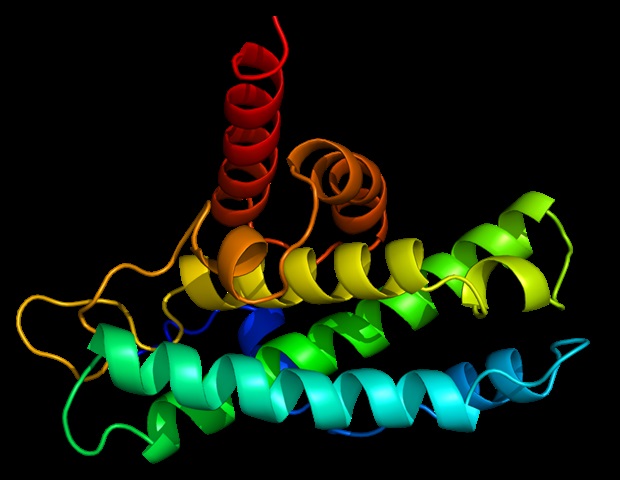

מחקר בראשות אוניברסיטת מישיגן סיפק ראיות משכנעות שיכולות לפתור תעלומה בסיסית בהרכב של סיבים הממלאים תפקיד באלצהיימר, פרקינסון ומחלות ניווניות

הפרעות מוחיות כמו פרקינסון (PD) או מחלת אלצהיימר (AD) מתחילות להתפתח בחולים הרבה יותר מוקדם מאשר הופעת התסמינים הקליניים הראשונים